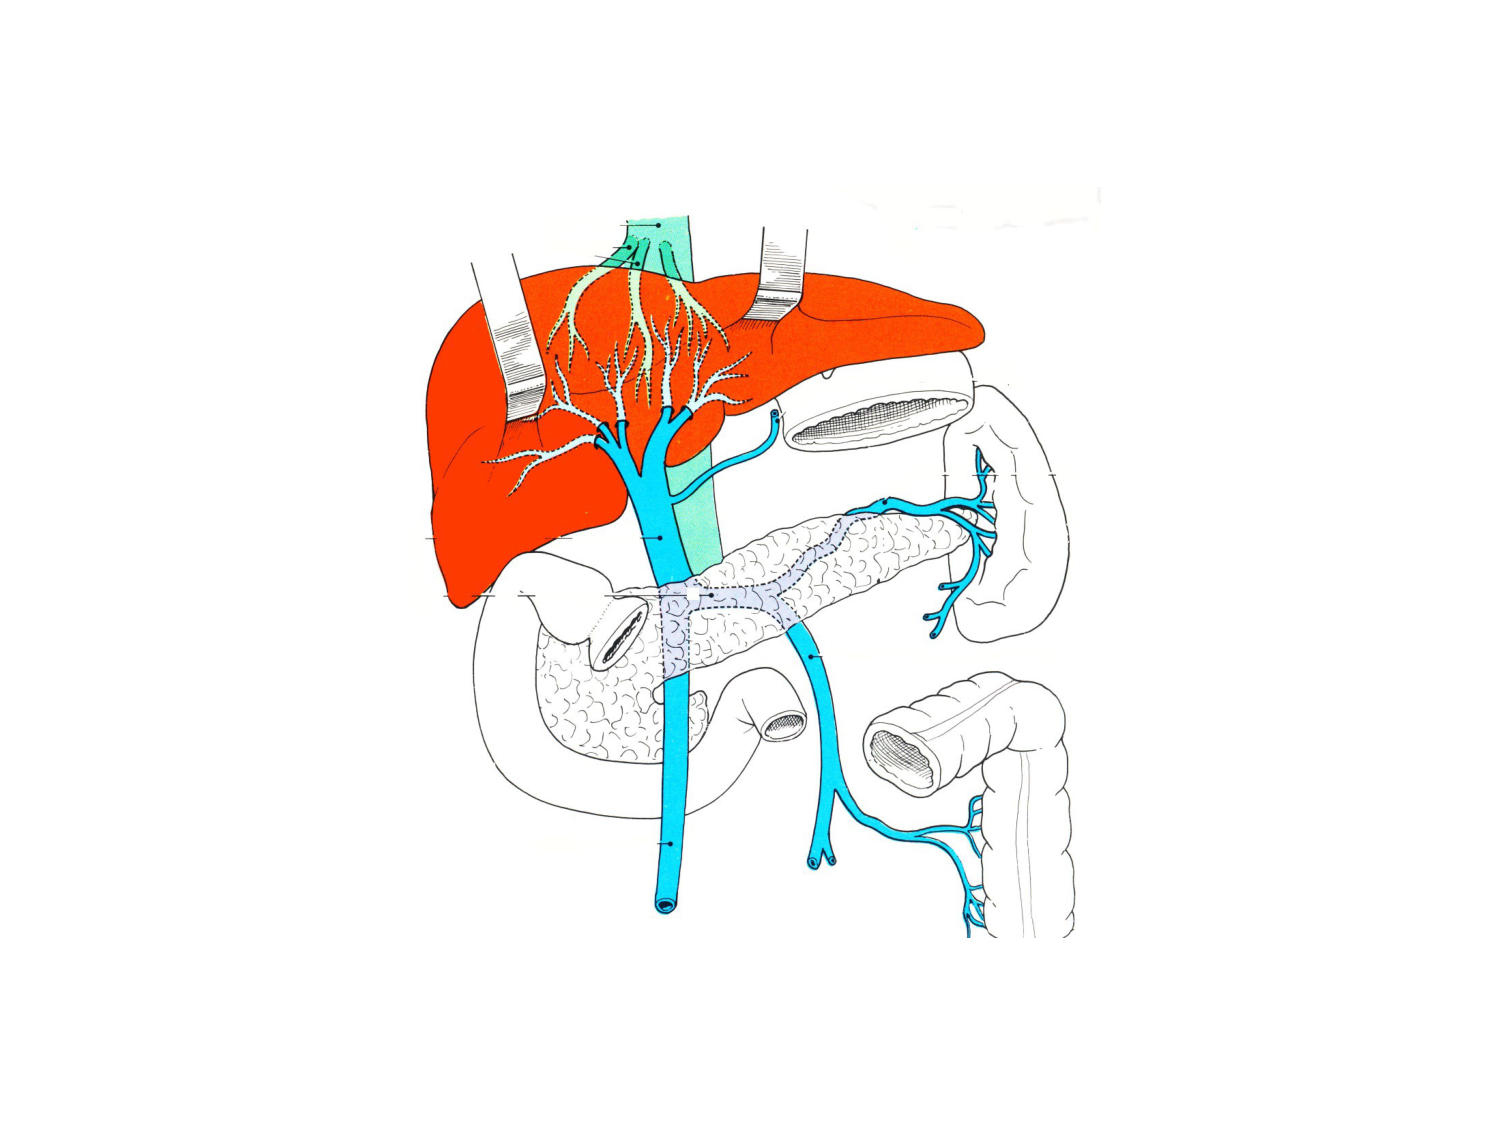

11.35 · Abdomen gros intestin foie rate pancreas vascularisation

Abdomen gros intestin foie rate pancreas vascularisation